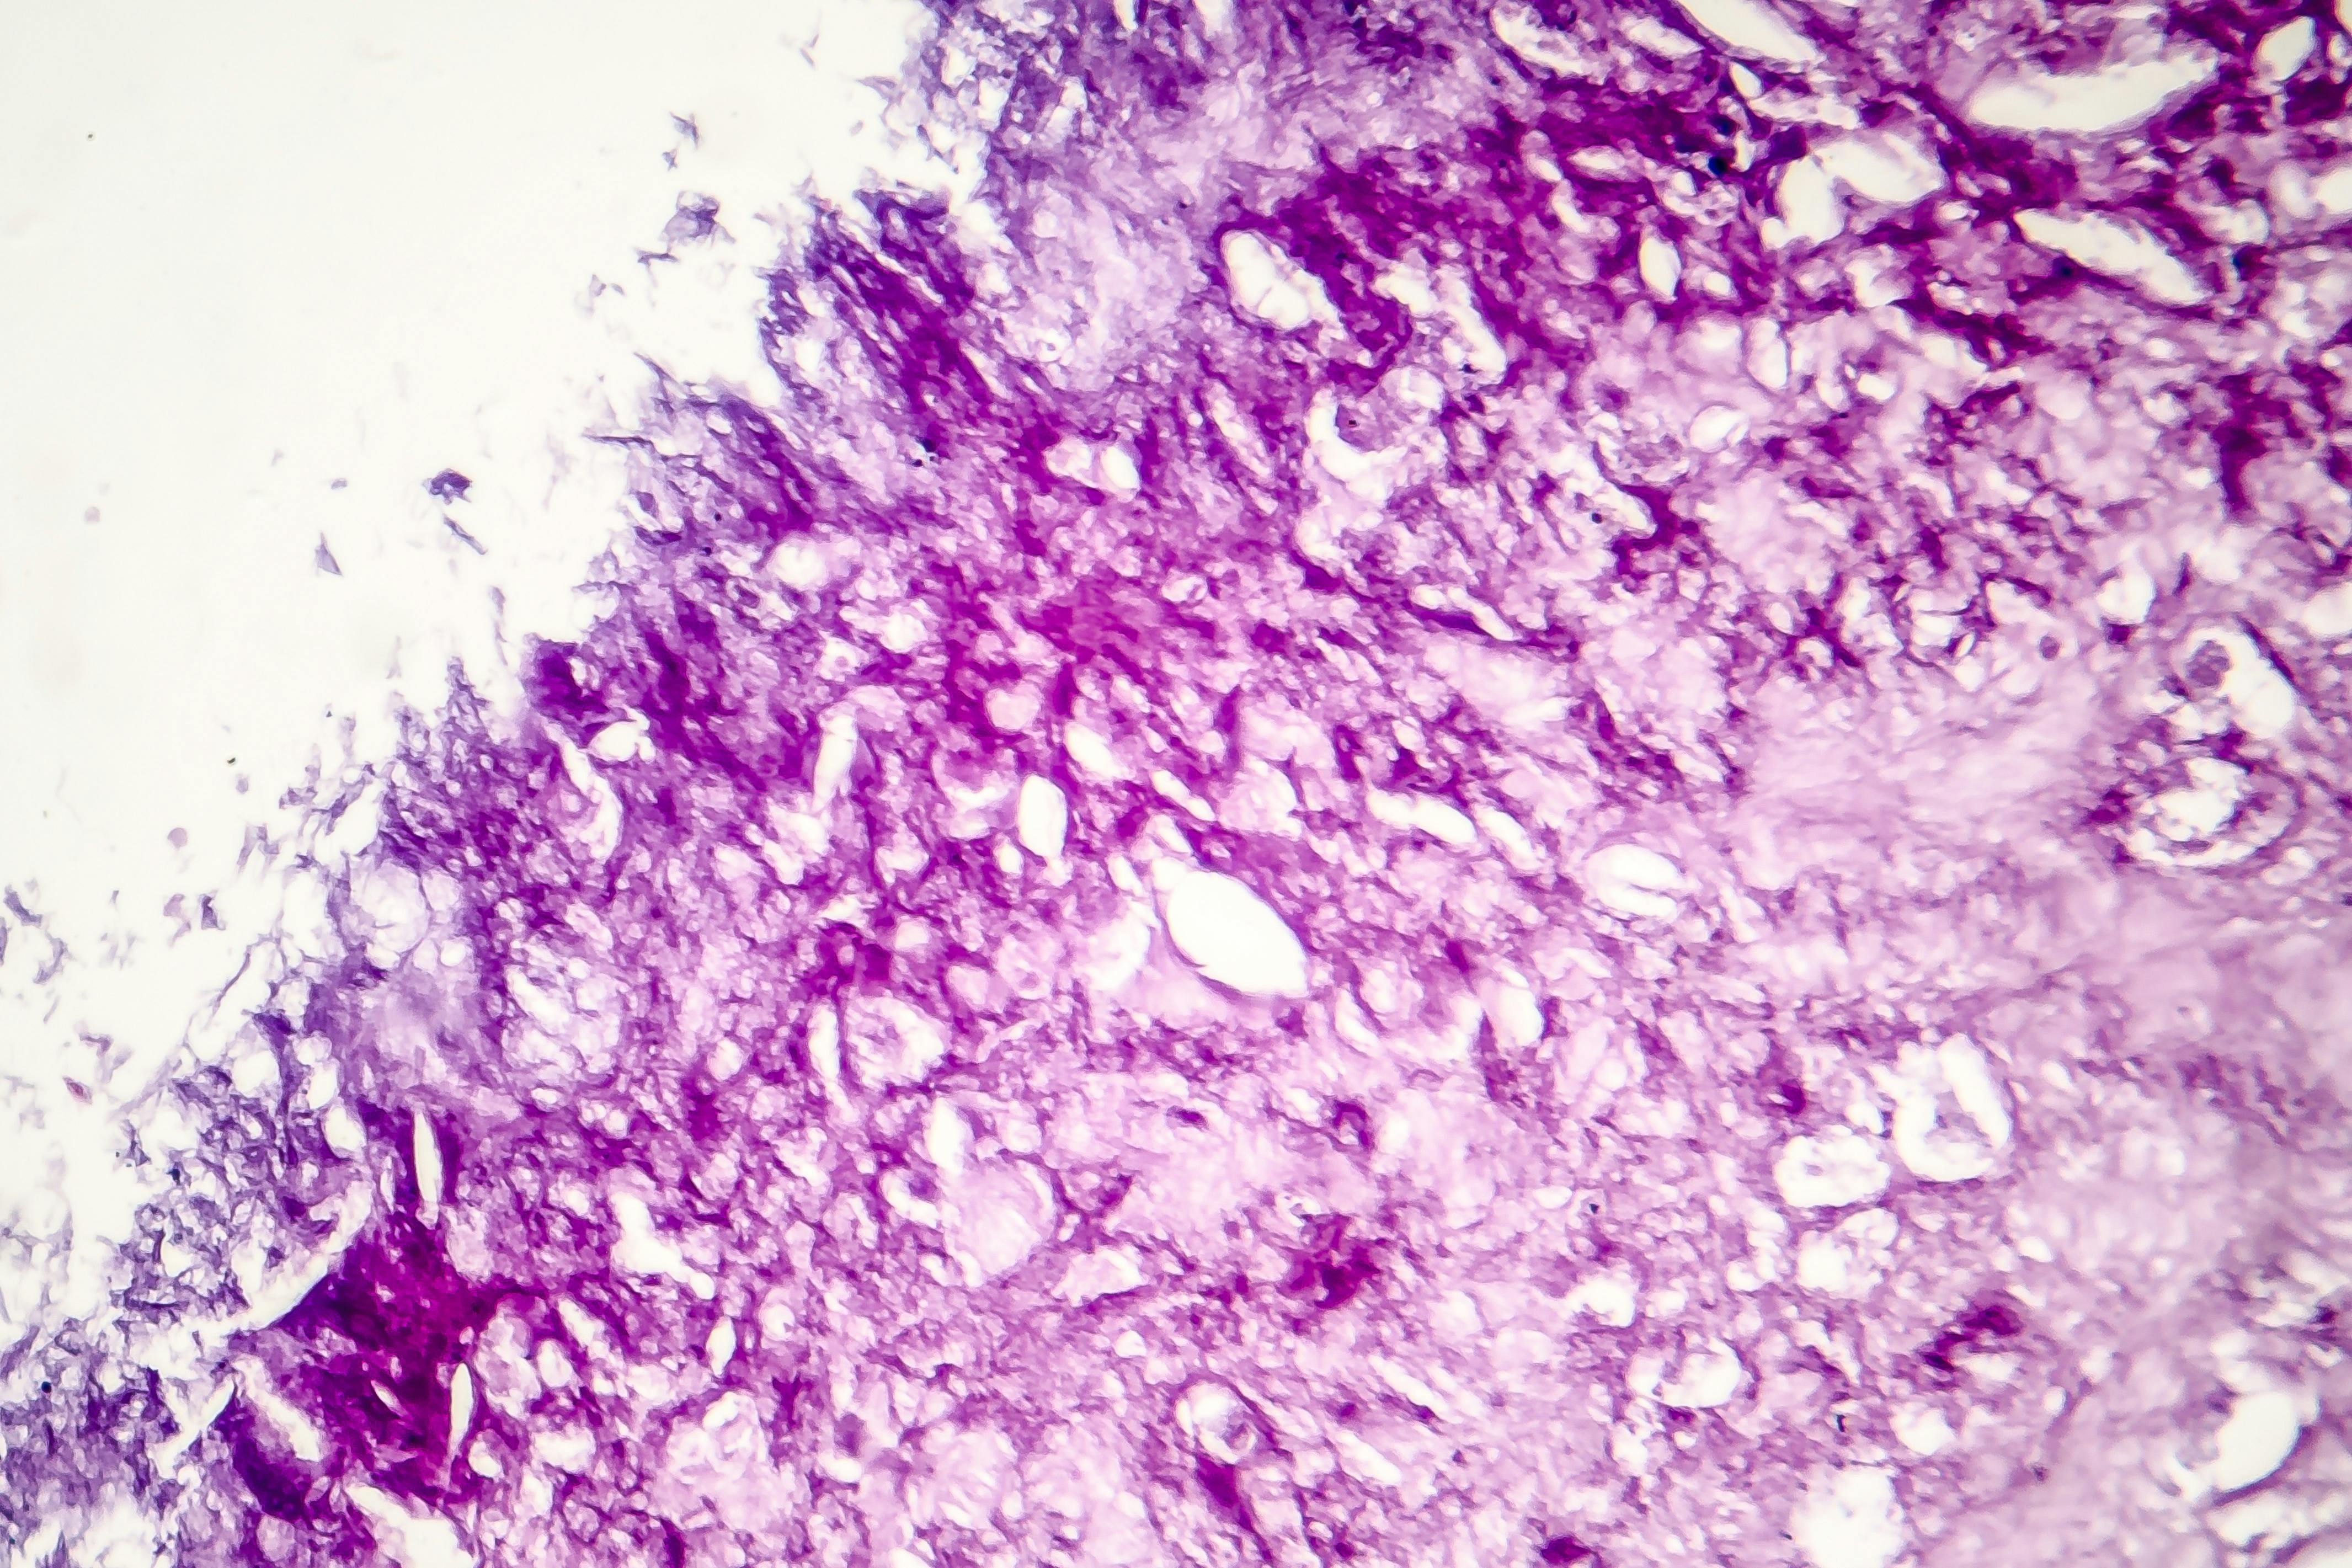

PathAI's PathAssist Derm, designed to assist in analyzing skin lesion images, has received FDA Breakthrough Device Designation, aiming to support pathologists in managing skin cancer cases more effectively.

PathAI announced that the U.S. Food and Drug Administration (FDA) has granted Breakthrough Device Designation to PathAssist Derm, designed to analyze digital pathology whole slide images (WSIs) of skin lesions and aid pathologists in their review.

By leveraging advanced AI technology to support case assessment and workflow prioritization, PathAssist Derm is designed to help pathologists manage rising skin cancer caseloads while maintaining diagnostic rigor.